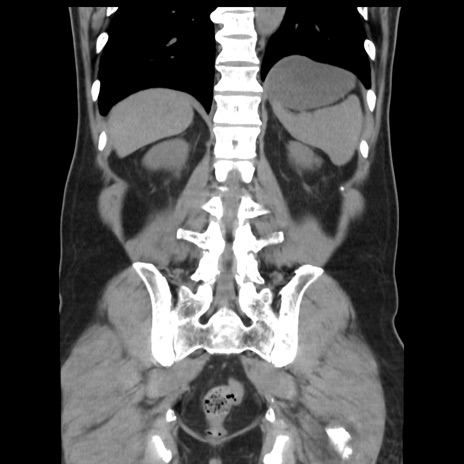

症例16(冠状断像)

【症例】 70歳代男性

【主訴】 腹痛、嘔吐

【現病歴】 約1ヶ月前より間欠的に腹痛と嘔吐あり、当院消化器内科を受診したところCTで多発する肝臓のLDAを指摘され、精査中であった。以降は消化器症状は安定していたが、2日前より嘔気と腹痛があり、同日より排便・排ガスが消失した。改善認めず、 本日、救急外来を受診した。

【既往歴】 大腸ポリープ切除後。

【身体所見】意識清明・会話良好、BT 36.3℃、BP 127/80mmHg、 P 80bpm、腹部:膨満あり、平坦・軟、上腹部正中および下腹部正中に圧痛あり、反跳痛なし、筋性防御なし。

【データ】WBC 7200、CRP 0.77